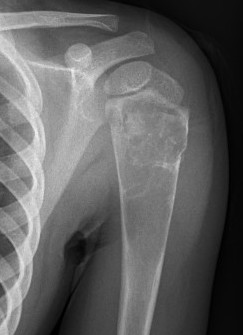

X-ray

Well-defined lucency

- thin sclerotic rim

- usually central

- thinned cortex with slight expansion

- thin internal septa

- can be multi-loculated

Fallen-Leaf (AKA fallen-fragment)

- with pathological fracture

- indicates that the lesion has no matrix and is fluid filled

Fallen leaf sign